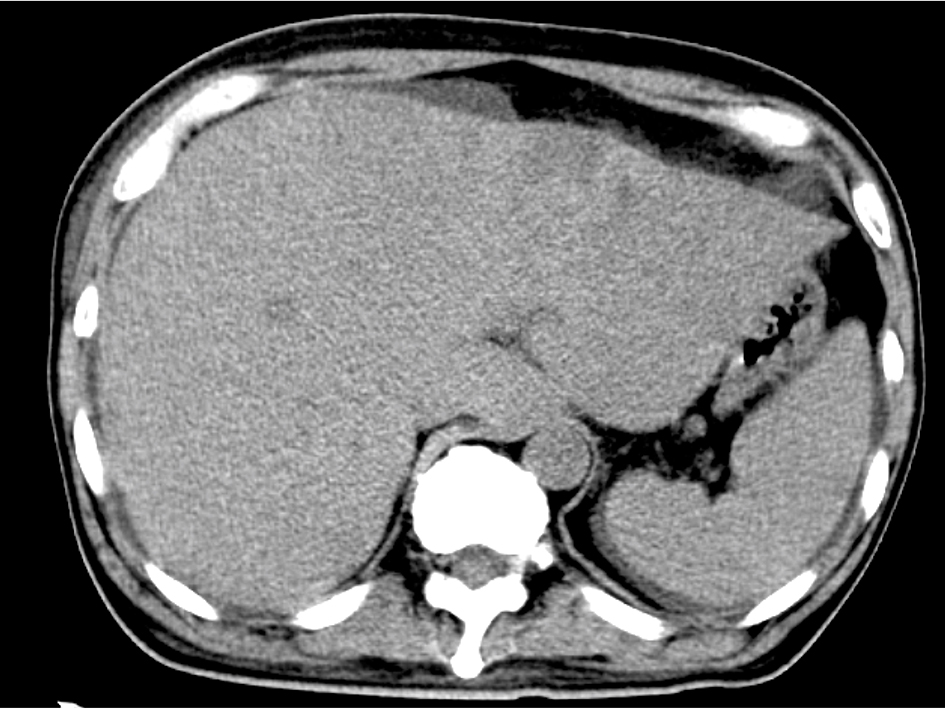

The blood test showed liver dysfunction and pre-renal dehydration. The circulating white blood cells were 13,440 cells/mL, hemoglobin was 12.4 g/dL and the platelet count was 27.8 × 104 cells/μL. The chemistry panel showed a potassium level of 5.1 mmol/L, chloride of 99 mmol/L, phosphate of 3.6 mg/dL and elevated levels of lactate dehydrogenase (LDH), aspartate aminotransferase (AST), alanine aminotransferase (ALT), alkaline phosphatase (ALP), total bilirubin (TB), direct bilirubin (DB) and C-reactive protein (CRP). Computed tomography and MRI revealed disseminated metastatic changes in lumbar spinal (Fig. 1), well-defined pulmonary tumors in the right lower and left upper lobes (Fig. 2) and an ambiguously bordered low-density area of the liver, predominantly in the left lobe as well as a moderate volume of ascites (Fig. 3).

![]() Click for large image | Figure 3. Abdominal CT. Diffuse hypo-density area in the swelled liver with ascites. |